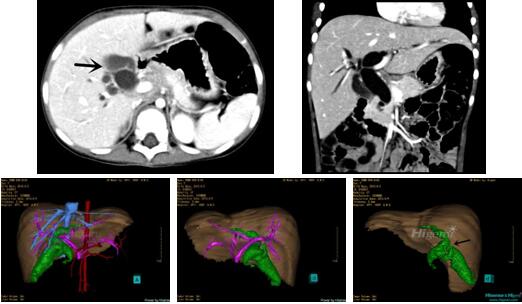

10、三维重建虚拟肝脏、胆道显像技术

三维虚拟肝脏技术是在二维影像学资料如CT等图像的基础上,通过三维重组软件和工具,比如青岛大学附属医院与海信医疗集团联合自主研发的海信计算机辅助手术系统(Hisense Computer Assisted Surgery,Hisense CAS),目前已投入临床并指导实际应用,利用该类系统对二维影像学的数据资料进行三维立体分析,重组形成立体的、有空间结构的、虚拟的肝脏三维图像。这项技术较传统的二维平面成像技术,有着明显的优势,3D虚拟肝脏技术可以构造出一个虚拟的、可视化的肝脏模型。通过对这种模型的观察,可以很容易地分辨出肝脏器官的组织结构、解剖特点,直观研究肝外胆总管的形态差异,明确肝内胆管的形态、走形、是否合并扩张、狭窄及结石,胰胆管合流的形态及共同通道内是否有狭窄、扩张和结石等病变情况,预先规划处理可能合并存在的肝内胆管扩张、狭窄或其他复杂胆道畸形,清晰地显示肝内脉管系统,包括门静脉、肝动脉及肝静脉的走行、分支,并可多角度、全方位观察病变胆道与其周围重要血管尤其是伴行的门静脉之间的解剖关系,大大提高了外科医师在术前对肝脏内部各管道结构及其变异判断的精确性和可靠性,精准地对病变进行判断和评估,还可根据患者自身的病变特点,制定出合理、个体化的手术方案,最大限度地降低术中和术后并发症发生率,并术中导航实时指导手术,提高手术的精准性和成功率。

图10:先天性胆管扩张症囊肿型三维重建虚拟肝脏、胆道显像

a 图为术前二维CT扫描图像,箭头所示为肝内胆管扩张;b 图为CT经多平面重组技术(MPR)图像后处理所得的重建图像,可显示胆总管明显扩张合并肝内胆管扩张;c 图为MRCP显示胆总管呈囊柱状扩张,直径>1 0 cm,伴肝内胆管扩张;d 图示Hisense CAS三维重建清晰显示肝脏、胆道系统及其与门静脉、肝动脉、肝静脉等之间的空间解剖关系;e 图示Hisense CAS可从任意角度以不同脏器组合显示,明确胆道系统与其伴行的门静脉系统的空间解剖关系;f 图示胆道系统立体形态及与肝脏整体的空间关系,箭头处显示肝内胆管狭窄部位发生于左右肝管汇入肝总管处。术前规划需行肝内胆管扩大成形术。

图11:先天性胆管扩张症梭状型三维重建虚拟肝脏、胆道显像

a 图为术前二维CT扫描图像,箭头指示肝内胆管扩张;b 图为CT经多平面重组技术(MPR)所得的重建图像,可粗略地判断病变胆管的位置;c 图示术前Hisense CAS三维重建清晰显示胆管的病理形态及其与肝内三套血管系统的解剖关系;d 图示胆道系统与其伴行的门静脉系统的空间解剖关系;e 图为胆道系统立体形态,箭头处指示迷走胆管,源自肝脏直接汇入胆总管。术前规划先将迷走胆管与肝总管吻合成形,再行肝总管空肠Roux-en-Y吻合术。